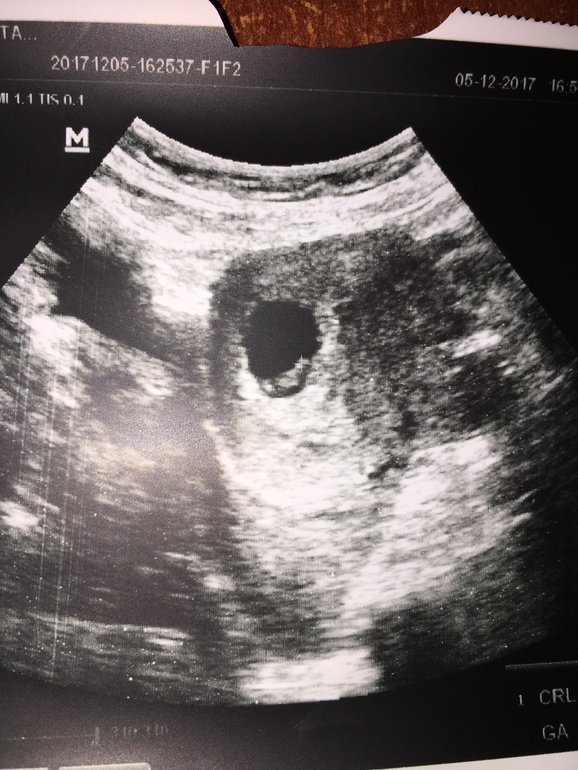

Поняла причину крови после ПА в начале беременности

Поздравляю Вас!!! Я тоже во вторник делала УЗИ- нашли сердечко, КТР 9 мм, сказали 7 недель))) У Вас малыш внизу лежит, а у меня наверху- что это значит? Прикрепление по передней стенке (у меня)? Так разволновалась, что у врача не спросила(((

Нашли эмбриончика и сердечко !)) Дюфастон при угрозе